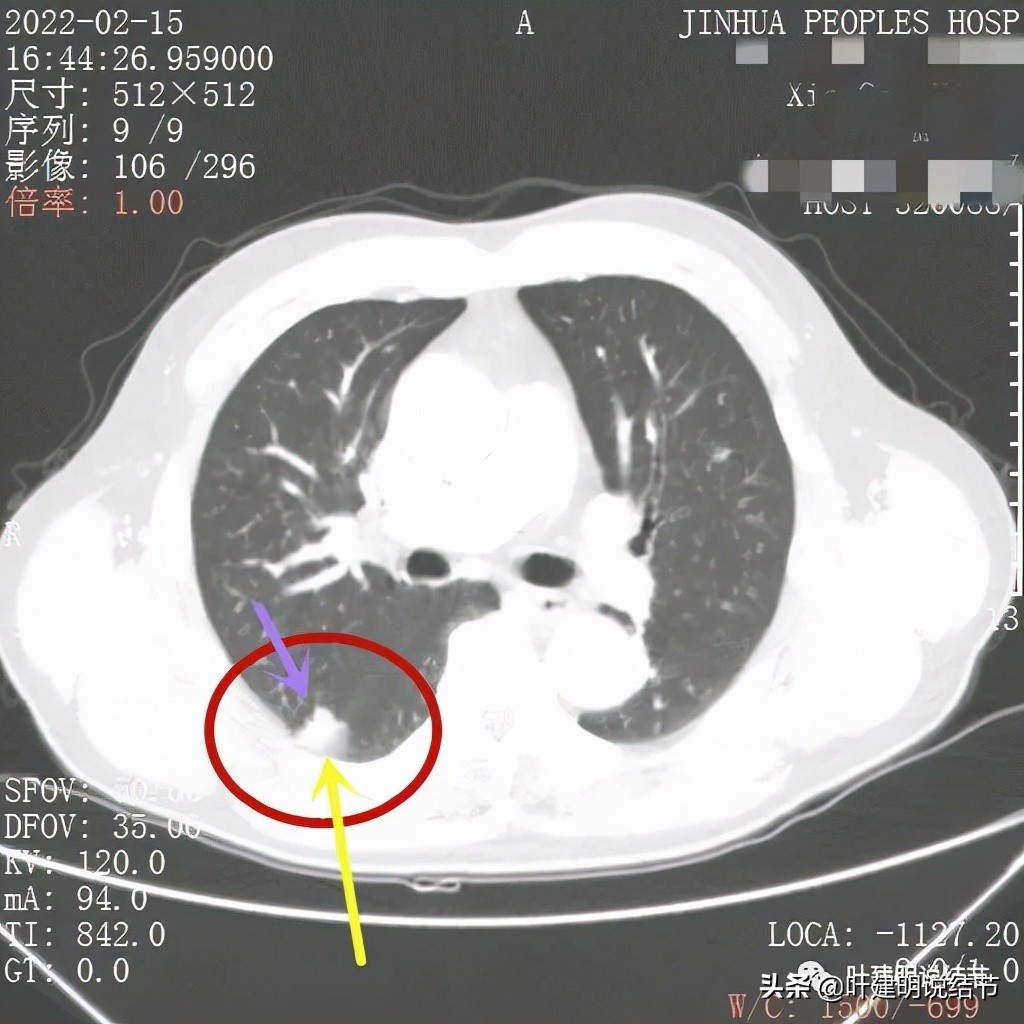

我们再来看薄层的CT图像:

病灶出现,虽然此层面还很小,但也是实性的,有微血管进入(桔色箭头)

上图更清楚显示血管进入病灶,病灶与胸膜间点状相接,感觉病灶有膨胀性,圆形或类圆形的

病赤边缘不平整,感觉毛糙(紫色箭头),此层也见血管征(桔色箭头)